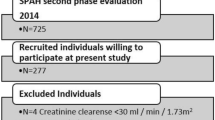

A total of 648 women were included in the current study, with a mean (SD) age of 79.7 (2.5) years at the baseline for this analysis. While 744 women had valid AAC and pQCT data at baseline, 94 women were excluded for bisphosphonate and/or warfarin use (n = 54 for bisphosphonates; n = 36 for warfarin; n = 4 for both), and another two women were excluded due to missing BMI data (Fig. 1). For longitudinal analyses, 551 women had valid data on AAC progression, while 645 women had valid pQCT bone change data from at least one bone site. There were no differences in demographic, AAC or pQCT bone measures between women with and without valid longitudinal AAC or bone data (data not shown). Characteristics of the final sample at baseline are presented in Table 1.

Participant flowchart showing how the study population was derived. For pQCT, participants were included if they had data available for at least one of the three scan sites. Therefore, the number of participants specified here for the longitudinal analysis differs from the number of participants actually included in the analysis for each individual bone measure